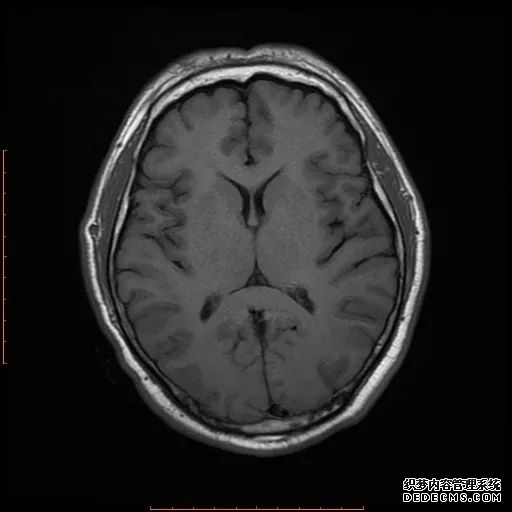

脑MRI显示尾状核、扁豆状核和脑梗头部T2/FLAIR呈双侧对称异常高信号。扩散限制涉及这些区域,其特征是扩散加权DWI(B-1000)上的高强度,ADC图上相应的减弱强度。

低血糖性脑病是一种代谢性脑病,它是由脑细胞对葡萄糖的供应和使用之间的不平衡引起的。脑MRI,尤其是DWI是诊断和预测该病预后的重要工具。

影像影响内囊后肢、大脑皮层(特别是枕叶和岛叶)、海马和基底节区,常是双边对称性的。